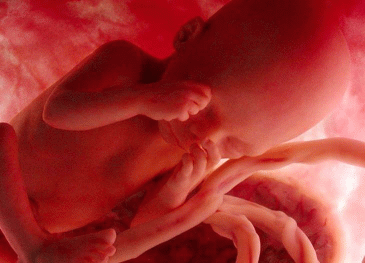

Il bambino ora prende quasi 200 grammi a settimana, pesa circa 1250 grammi e i suoi polmoni continuano ad esercitarsi nella respirazione. La testa cresce per fare spazio al cervello che ogni giorno vede nascere miliardi di nuovi neuroni, scalcia a più non posso ed è possibile contare i suoi movimenti per verificare il suo benessere e controllare che sia ben ossigenato. Per farlo, mettiti sdraiata su un fianco ogni giorno alla stessa ora, rilassati e concentrati su di lui, poi conta quanto tempo occorre al tuo piccolo per farsi sentire almeno dieci volte, conterai calci, pugni, singhiozzi e anche movimenti della testa e del sederino. La buona regola è che non servano più di due ore per arrivare a dieci.

Il bambino continua a crescere e ormai occupa quasi interamente lo spazio nell’utero.È possibile avvertire movimenti netti e precisi, al punto che potresti distinguere bene di quale parte del corpo si tratta, se la testa, il sederino o anche la schiena.

Il bambino è arrivato a circa 1400 grammi, è più cicciottello e la sua pelle è più liscia e rosea.Con le sue continue capriole, potrebbe trovare la posizione definitiva per la nascita.

Ora il piccolo pesa circa 1600 grammi, ogni giorno che passa mette su il grasso sottocutaneo e la pelle è meno rugosa, lo spazio disponibile è poco e i suoi movimenti sono meno “tellurici”.

L’utero è arrivato a circa 12 centimetri sopra la linea ombelicale trasversa e il piccolo pesa circa 1800 grammi ed è lungo circa 40 centimetri.

La peluria che lo ricopre comincia a scomparire mentre la vernice caseosa lo ricopre totalmente. Gli occhi distinguono la luce dal buio e, soprattutto, distingue il caldo dal freddo, al punto tale che si muove se viene posta una fonte di calore vicino alla pancia.